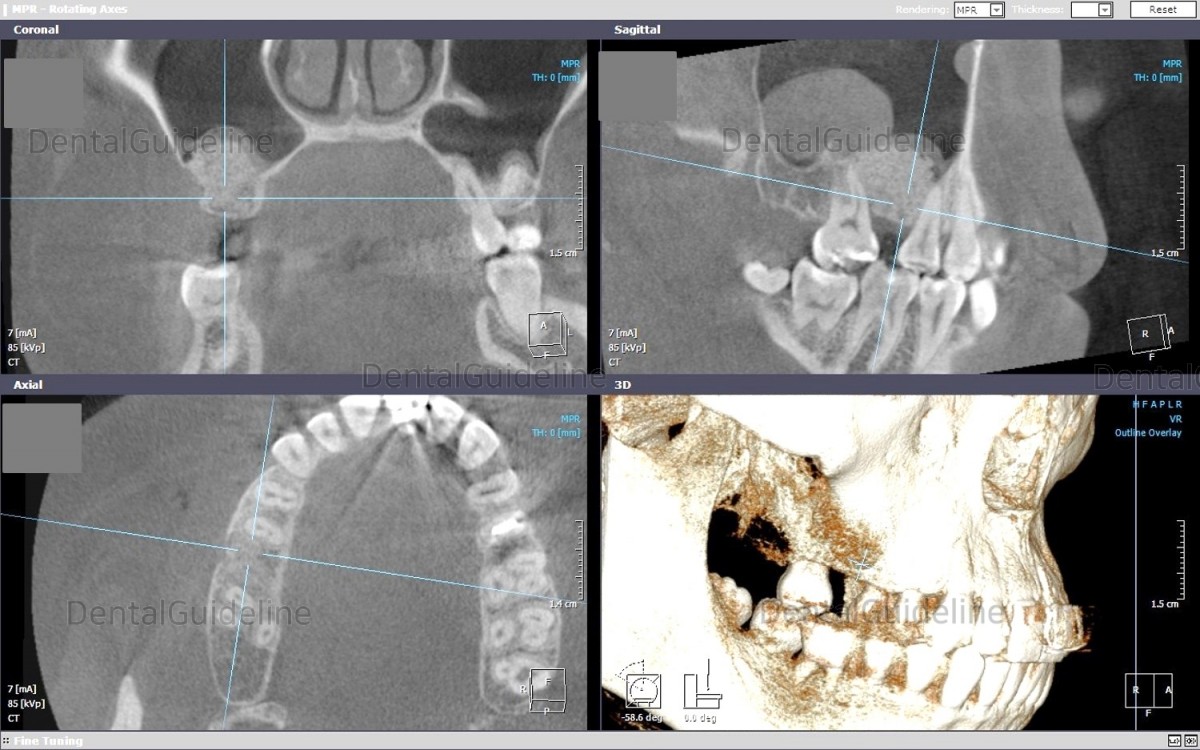

12. .CBCT after the graft.

13. Photo 2 months later.![]()